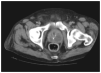

En las horas siguientes presentó picos febriles, deterioro respiratorio y hemodinámico, por lo que precisó intubación orotraqueal, conexión a ventilación mecánica e inicio de perfusión de fármacos vasoactivos. Cursó clínicamente con síndrome de distrés respiratorio agudo (SDRA) y shock séptico. Se recibieron los resultados de los cultivos, que fueron positivos, en sangre y orina para Escherichia coli, sensible a ceftazidima (se suspendió la gentamicina). Se solicitó una tomografía computarizada (TC) abdominopélvica en la que se observaba una próstata aumentada de tamaño, con 2 áreas hipodensas intraprostáticas de 2,5 y 4 cm de diámetro, respectivamente, y contorno irregular, todo ello compatible con un cuadro de prostatitis aguda y abscesos intraprostáticos (fig. 1), diagnóstico confirmado por ecografía transrectal. Se procedió a drenaje quirúrgico del absceso y resección transuretral (RTU) de la próstata, practicándose una talla vesical y sondaje uretral con lavado continuo. En los días siguientes se observó una mejoría lentamente progresiva de su insuficiencia respiratoria e inestabilidad hemodinámica, con normalización de la fiebre y de la leucocitosis. Fue dado de alta a la planta de urología 10 días después de su ingreso, y con posterioridad a su domicilio, con un mínimo grado de incontinencia urinaria. El informe anatomopatológico reveló una prostatitis aguda y crónica, sin signos de malignidad.

Figura 1. Áreas hipodensas intraprostáticas de 2,5 y 4 cm de diámetro (flechas) compatibles con abscesos prostáticos.